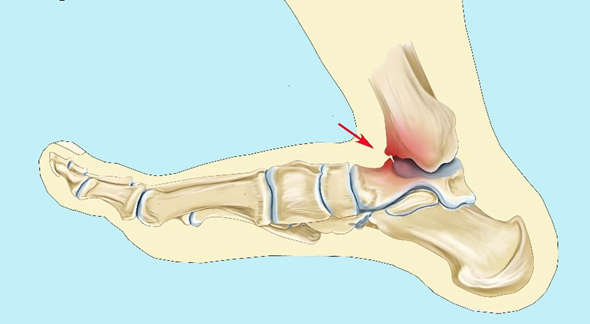

图3:胫骨下唇与距骨颈部重复撞击,形成骨赘

▶踝关节过度跖屈,造成踝关节前关节囊反复被牵拉,胫骨下唇与距骨颈部重复撞击,形成骨赘或关节游离体。

▶踝关节反复扭伤导致关节不稳定,导致骨和滑膜的增生。

▶踝关节运动姿态不正确,致使关节软骨遭受不断累积的破坏性应力。